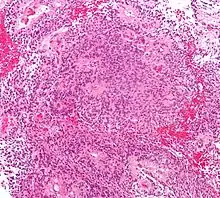

Astrocytome

Divers systèmes de catégories ont été proposés dans la littérature au fil du temps pour classer la malignité des astrocytomes. Depuis 1993, le système d'évaluation à quatre niveaux proposé par l' Organisation mondiale de la santé (OMS) est le plus largement utilisé et appliqué. Elle est basée sur quatre caractéristiques histologiques : augmentation de la densité cellulaire, mitose, prolifération endothéliale et nécrose. Par la suite, les astrocytomes de grade I, tels que les astrocytomes pilocytiques, sont généralement d'histologie bénigne. Astrocytomes II. Les grades (diffus) montrent une densité cellulaire accrue comme seule caractéristique histologique et sont des néoplasmes avec un degré d'infiltration inférieur. Les astrocytomes III montrent une mitose importante. grade (anaplasique). Et la prolifération ou la nécrose endothéliale sont observées dans les astrocytomes IV. degrés, les soi-disant glioblastomes.

Astrocytomes anaplasiques

L'astrocytome anaplasique est une tumeur cérébrale maligne caractérisée par une croissance diffuse, une densité cellulaire accrue et des figures de division nucléaire. Elle est issue d'une population cellulaire spécifique du système nerveux central, les astrocytes. Selon la classification OMS des tumeurs du système nerveux central, la tumeur correspond à une tumeur de grade III.

Les tumeurs des cellules gliales les plus courantes et les plus malignes sont les glioblastomes. Ils consistent en une masse hétérogène de cellules d'astrocytome peu différenciées principalement chez l'adulte. Ils surviennent généralement dans les hémisphères cérébraux, plus rarement dans le tronc cérébral ou la moelle épinière. Sauf dans de très rares cas, comme toutes les tumeurs cérébrales, elles ne s'étendent pas au-delà des structures du système nerveux central.